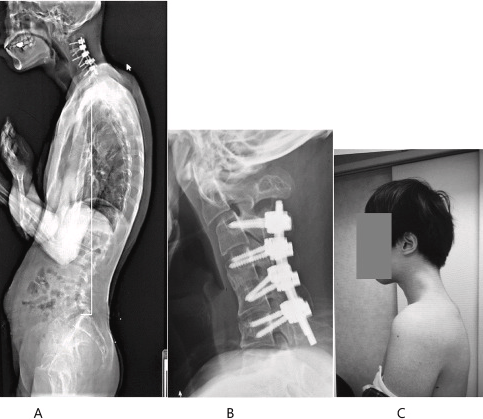

Η μαγνητική τομογραφία αποκάλυψε εκτεταμένες βλάβες στην αυχενική μοίρα της σπονδυλικής του στήλης: μετατόπιση, ουλώδη ιστό και σοβαρή υπερδιάταση λόγω της χρόνιας κακής στάσης.

Αρχικά, οι γιατροί επιχείρησαν να αντιμετωπίσουν την κατάσταση με την εφαρμογή αυχενικού κολάρου, χωρίς επιτυχία. Ο ασθενής άρχισε να παραπονιέται για μούδιασμα και περιορισμένη κινητικότητα. Τελικά, υποβλήθηκε σε χειρουργική επέμβαση: αφαιρέθηκε κατεστραμμένο τμήμα της σπονδυλικής στήλης και ουλώδης ιστός, ενώ τοποθετήθηκαν βίδες και μεταλλικές ράβδοι για τη σταθεροποίηση του αυχένα.

Έξι μήνες μετά την επέμβαση, ο άνδρας κατάφερε να επανακτήσει πλήρως τη σωστή στάση του σώματος και την ικανότητα να σηκώνει το κεφάλι του κανονικά.